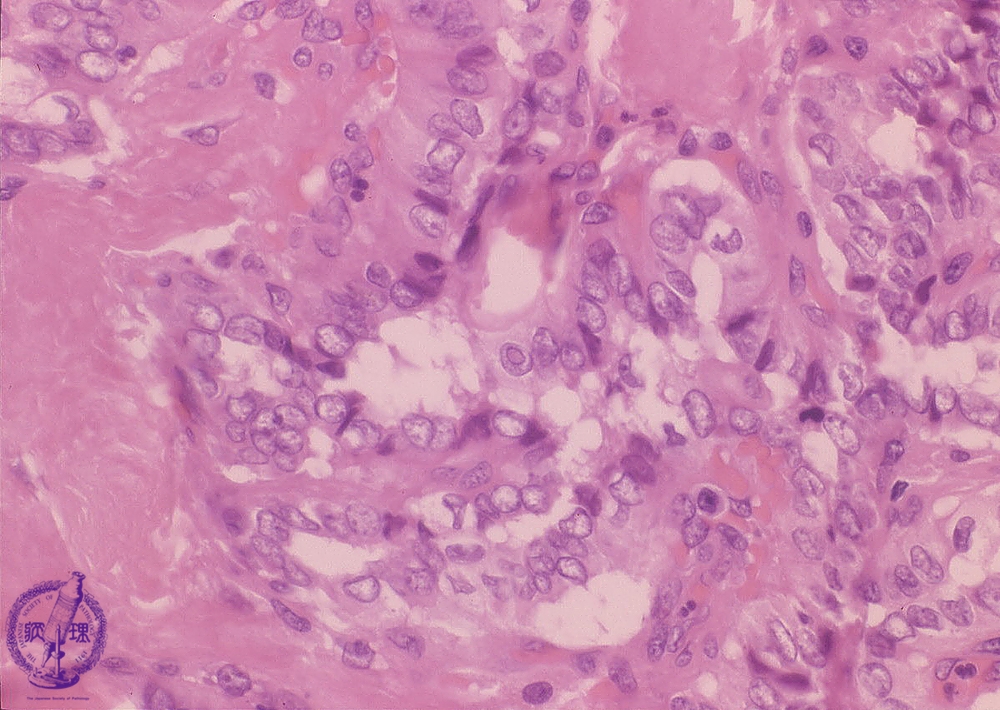

- ★(8)Papillary carcinoma of the thyroid

Microscopic findings (HE stain, high power view). Ground glass nuclei, nuclear grooves (arrow heads), and intranuclear cytoplasmic inclusions (arrows) are all apparent and are distinctive nuclear features of papillary carcinoma.